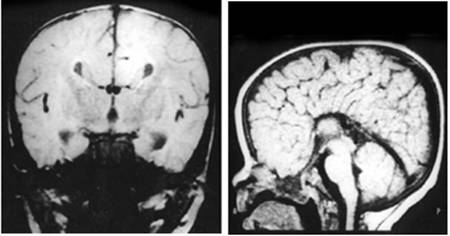

Figure 1

Clinical and image aspects of patient 1